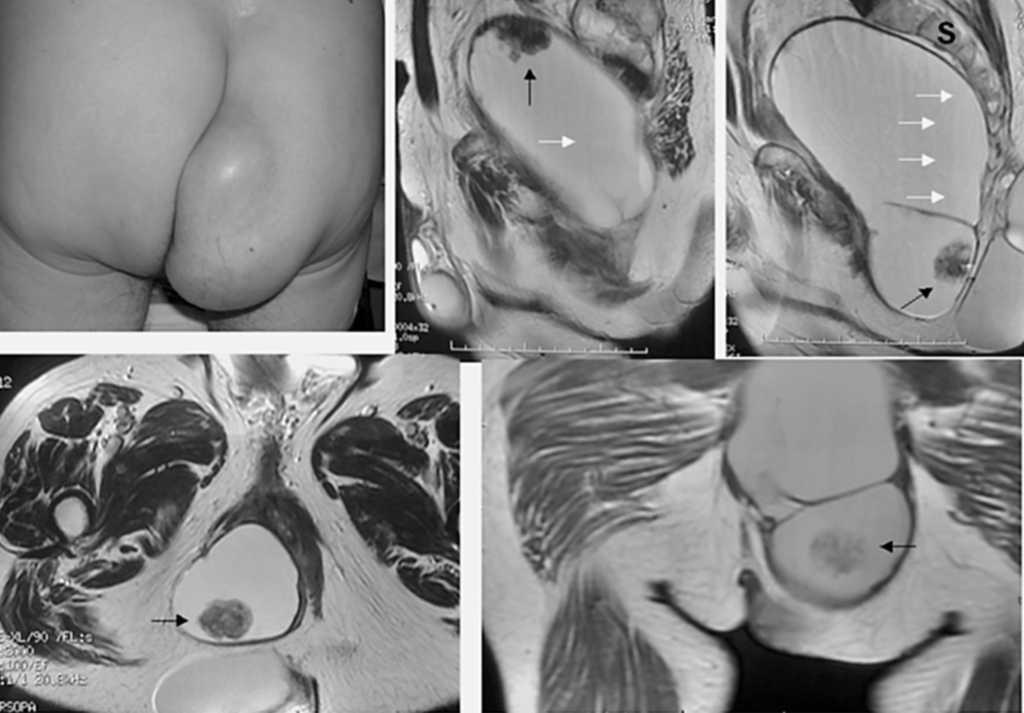

Fig. 1.

Paciente varón de 70 años de edad, que presenta tumoración glútea de muchos años de evolución que ha aumentado de tamaño produciéndole urgencia defecatoria y dolor.

A la exploración, presenta masa de consistencia elástica, lobulada que al tacto rectal provoca compresión extrínseca.

En la resonancia magnética (RM) se observa una tumoración pelviana gigante (25 x 12 x 10 cm) de localización presacra (S: sacro), tabicada y con lobulaciones, que se extiende por el tejido celular subcutáneo de la nalga y el periné. Se sospecha de la existencia de material mucinoso y contenido graso en su interior debido a la presencia de artefactos de desplazamiento químico (flechas blancas). En el seno de la lesión se identifican al menos 2 nódulos sólidos que se muestran como engrosamiento irregular de la pared (flechas negras). La lesión, predominantemente quística y encapsulada, produce desplazamiento anterior de todos los órganos pelvianos pero sin aparentes signos infiltrativos.

Dichos hallazgos morfológicos y el tiempo de evolución serían compatibles con un teratoma sacrococcígeo maduro.

Tras la éxeresis de la lesión se confirma el diagnóstico de teratoma quístico maligno en el que se ha malignizado el componente epitelial en dos focos coincidentes con los nódulos sólidos.